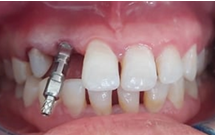

On the day of implant placement : (Figures 6,7). The implant was placed 7 years after the fall of 12 (loss of tooth due to trauma) in a completely healed site. 10 days after implant placement: (Figure 8). A temporary mesially extended bridge supported on 13 was cemented .

Figure 6 Placement of the implant + screw cover + suture.

6 months after implant placement: (Figure 9). A second surgical step for the placement of the healing screw to shape the soft tissue, especially the emergence profile.

Figure 9 Placement of the healing screw (6 months after osseointegration).